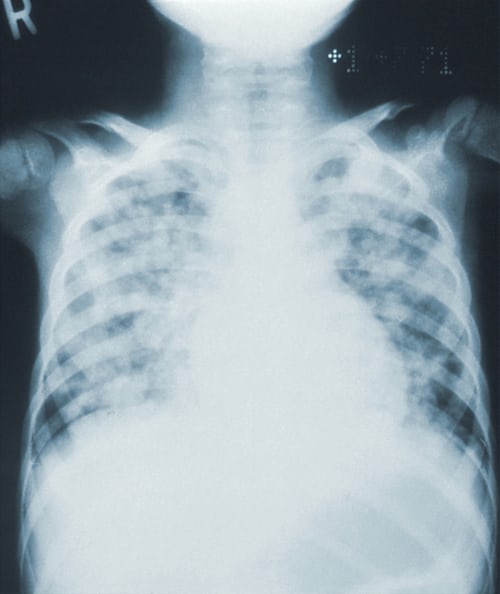

- 영상 검사: 폐렴 의심 시 X-ray 검사로 흉부 상태 확인 필요 .